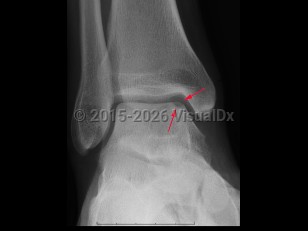

Osteochondral defect

An osteochondral defect is a rare condition of osteonecrosis of the subchondral bone, characterized by a loose bone fragment and articular cartridge which is partially or completely detached from underlying bone. Joints most commonly affected are knee, elbow, and ankle. Symptoms include localized pain following athletic injury or overuse, more often in boys than girls. If the fragment becomes lodged in the joint, the patient may experience increased pain, tenderness, locking, or crepitus of the joint. Treatment depends on growth stage of affected patient. Juveniles with open growth plates may be treated conservatively and nonsurgically. Adults who are skeletally mature may undergo arthroscopic repair.